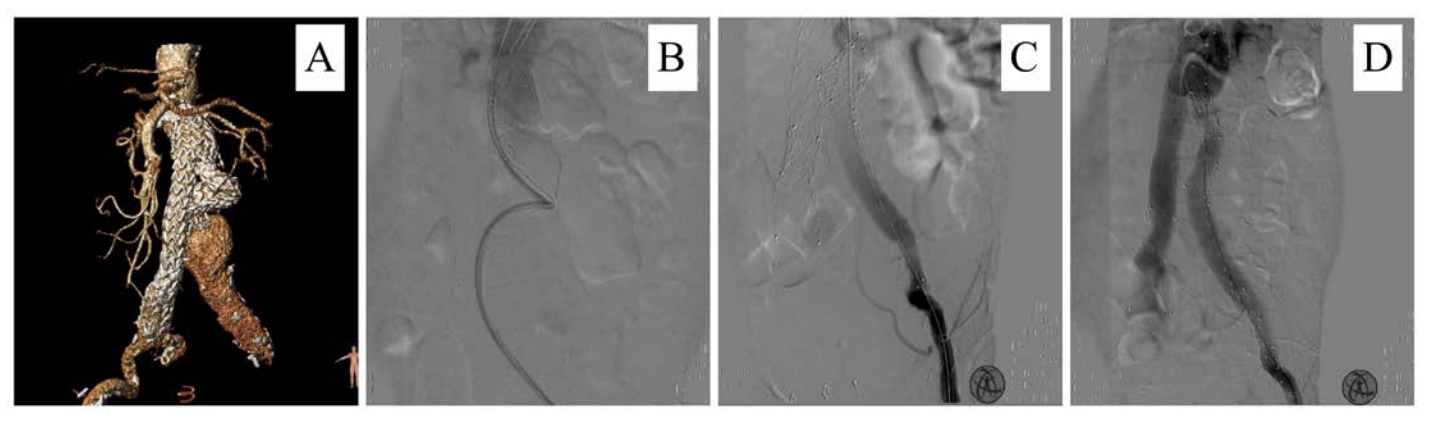

The total incidence of postoperative endoleak was 24.3%, with type II representing 60% of these cases. All other types of endoleak represented an indication for re-intervention (Figure 3, 4). Type II endoleak was an indication for intervention only when sac expansion was detected. We adopted a conservative management approach with a close follow-up strategy with the rest of the cases (Figure 5). This strategy proved safe and effective, with no reported adverse events or ruptures related to this type of endoleak. This is consistent with the Eurostar registry and the report published by Sidloff et al36 after following up on 175 cases of type II endoleak among a cohort of 904 cases of EVAR done in the UK between 1995 and 2013.